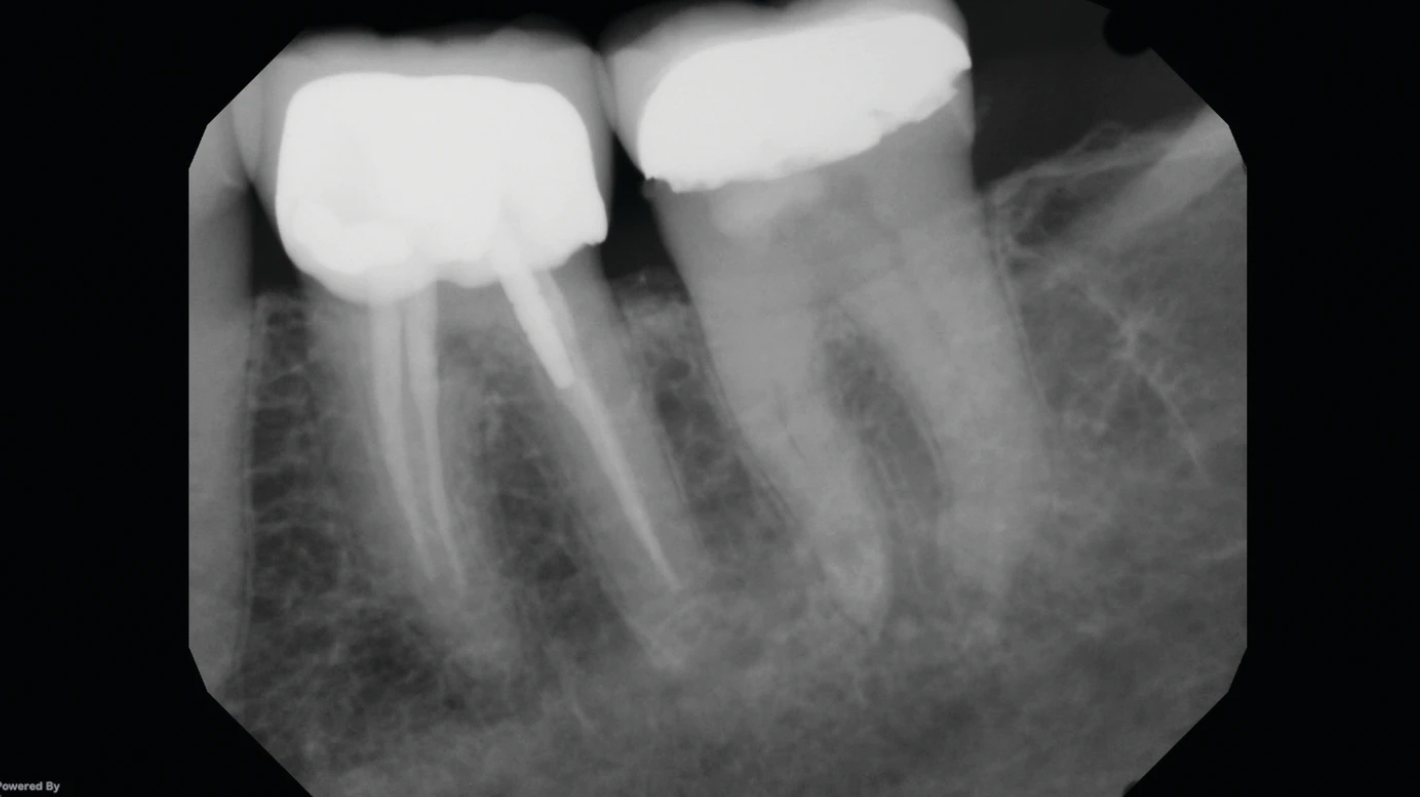

For those on the fence due to cost, there are 2-D upgradeable units. But with the declining costs of 3-D technology during the last 10 years, it’s debatable whether it’s worthwhile to postpone what will soon be mainstream. As I’ve often written, better to immerse oneself in the technology and become comfortable with what your competition already knows; 3-D is the present and the future. Those who wait to take the plunge risk being left behind. Look at the visual differences between 2-D and 3-D and tell me you don’t need this.